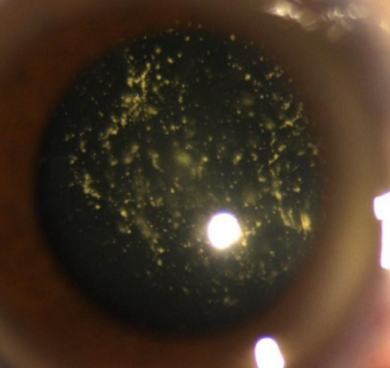

The image shows tobacco dust appearance (Shaffer's sign) suggestive of _____ retinal detatchment

What pathology is shown in the given image? _____